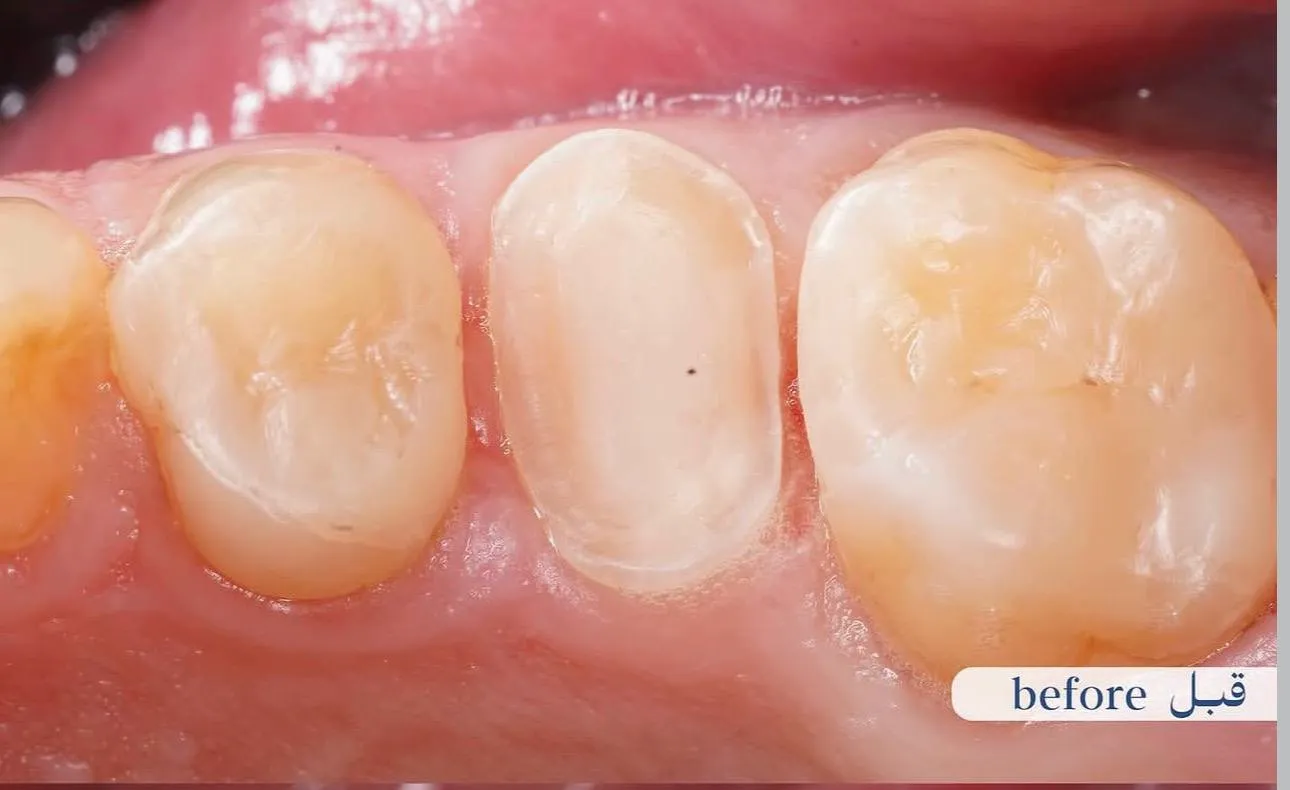

قبل